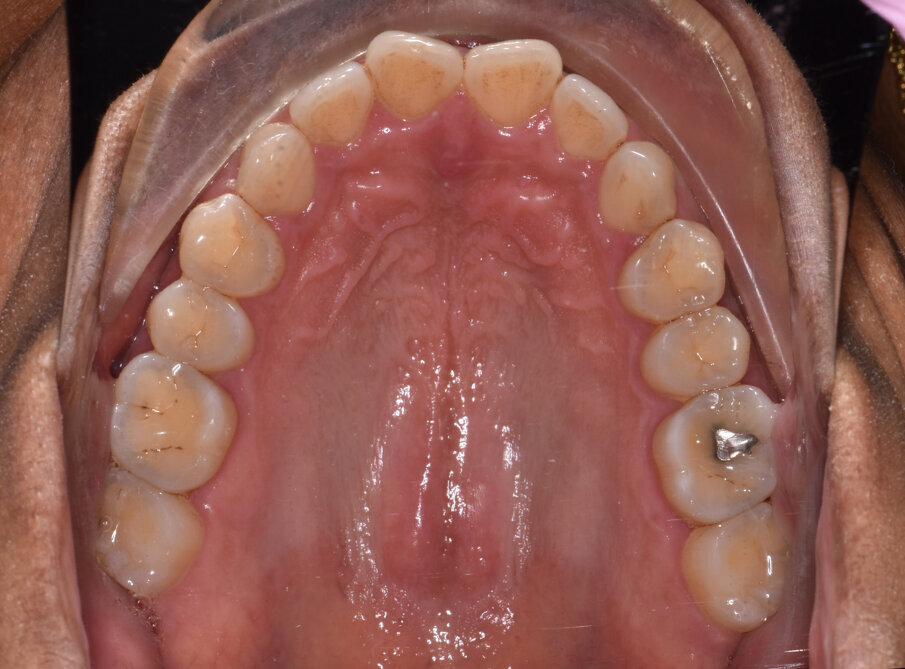

A 56-year-old female patient presented with a Class III malocclusion, anterior crowding and a 2-3 mm anterior open bite. Clinical photographs showed an ideal incisor display upon smiling. The panoramic film was unremarkable, and the lateral cephalometric film revealed a negative 1 mm overjet. (Figs. 1 to 10)

Specifically, the plan prescribed upper arch expansion and bilateral molar and second premolar intrusion of 3 mm. To support intrusion and prevent reciprocal lifting of the aligners, 4 mm wide occlusally beveled retentive attachments were designed and placed on the premolars. (Fig. 11)

Lower arch expansion and interproximal reduction of 0.5 mm were prescribed on all of the lower incisors from mesial of canine to mesial of canine before the 19th aligner. (Fig. 13) IPR would allow retraction to assist the Class III elastic correction of the negative overjet. Additionally, since counterclockwise autorotation of the mandible would project the lower incisors anteriorly, retraction would also assist in mitigating this effect.